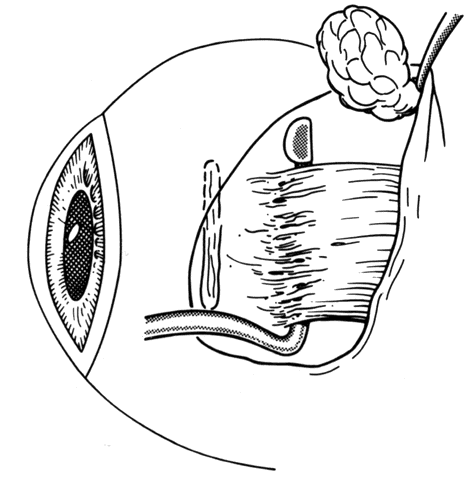

In some situations, a portion of a horizontal rectus may be left at the insertion site (Figs. 9 and 10). The muscle is usually split at the time of the initial procedure, and this can cause a shift of the distribution of force at the insertion and cause vertical misalignment. The pattern of the strabismus and the details of the previous surgery should provide clues to the problem and allow a logical approach for correcting the vertical deviation. Suspicions should be confirmed by careful dissection and exploration of the region of the muscle insertion. The importance of careful evaluation and elimination of mechanical restrictions cannot be overemphasized.4,10

Fig. 9. Residual exotropia or hypertropia can occur if a portion of the lateral rectus muscle is not recessed with the first procedure. To prevent this, care must be taken to incorporate all portions of the tendon when recessing an extraocular muscle.

Fig. 10. The pole test, or sweeping a Stevens muscle hook anterior to the insertion, will ensure that the entire tendon is on the Jameson muscle hook.